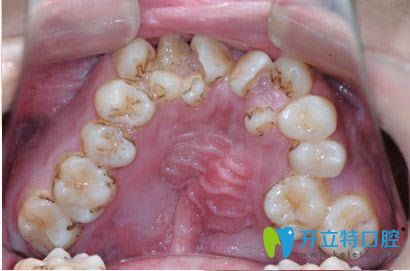

牙齒不齊容易引起牙周病及齲齒

張?jiān)洪L(zhǎng)表示,首先,年齡大了以后,牙齒是否會(huì)早掉,主要取決于牙周情況的好壞(包括牙周膜、牙槽骨、牙齦),還有就是蛀牙齲齒的因素。整個(gè)牙齒被蛀空了容易掉,當(dāng)牙周長(zhǎng)期炎癥侵蝕,導(dǎo)致骨頭吸收,就如水土流失一般,牙齒也容易掉。而引起牙周炎的往往是牙齒菌斑微生物和牙結(jié)石。